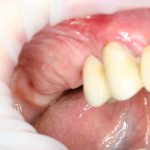

Вот клиническая картина через 4 месяца после ранее проведенной имплантации с остеопластикой:

Как видишь, коллеги из недалекой дружественной страны не осилили снятие швов. Мне это не нравится, хотя и объясняет, почему люди готовы ехать за тыщи километров ради 20-минутной операции удаления зуба мудрости.

Ну хорошо. Швы сняли. Делаем разрез. Обрати внимание, что после всех проведенных операций у нас остается очень небольшой по ширине слой жевательной слизистой оболочки: